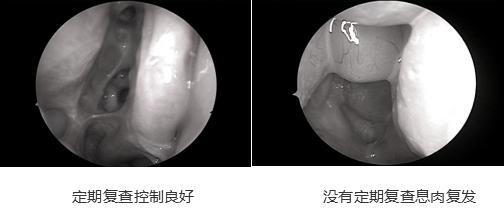

也有一些患者不重视复诊随访,术后一次也不来复诊。虽然手术做得非常好,但几个月后甚至几年后患者的鼻子又出现问题了,当再来检查时,会发现术腔粘连,息肉复发,没在息肉能控制的时间及时用药导致需要修复性手术,悔之晚矣。

第一次复诊结束后,医生会根据情况安排接下来的复诊时间,一般会在术后一个月。以后会根据患者的情况延长随后的复诊时间。一般患者恢复时间会因人而异,但如果顺利的话三个月到半年时间基本病情就稳定了,而嗜酸性粒细胞优势型鼻窦炎鼻息肉患者则需要长期的随访。